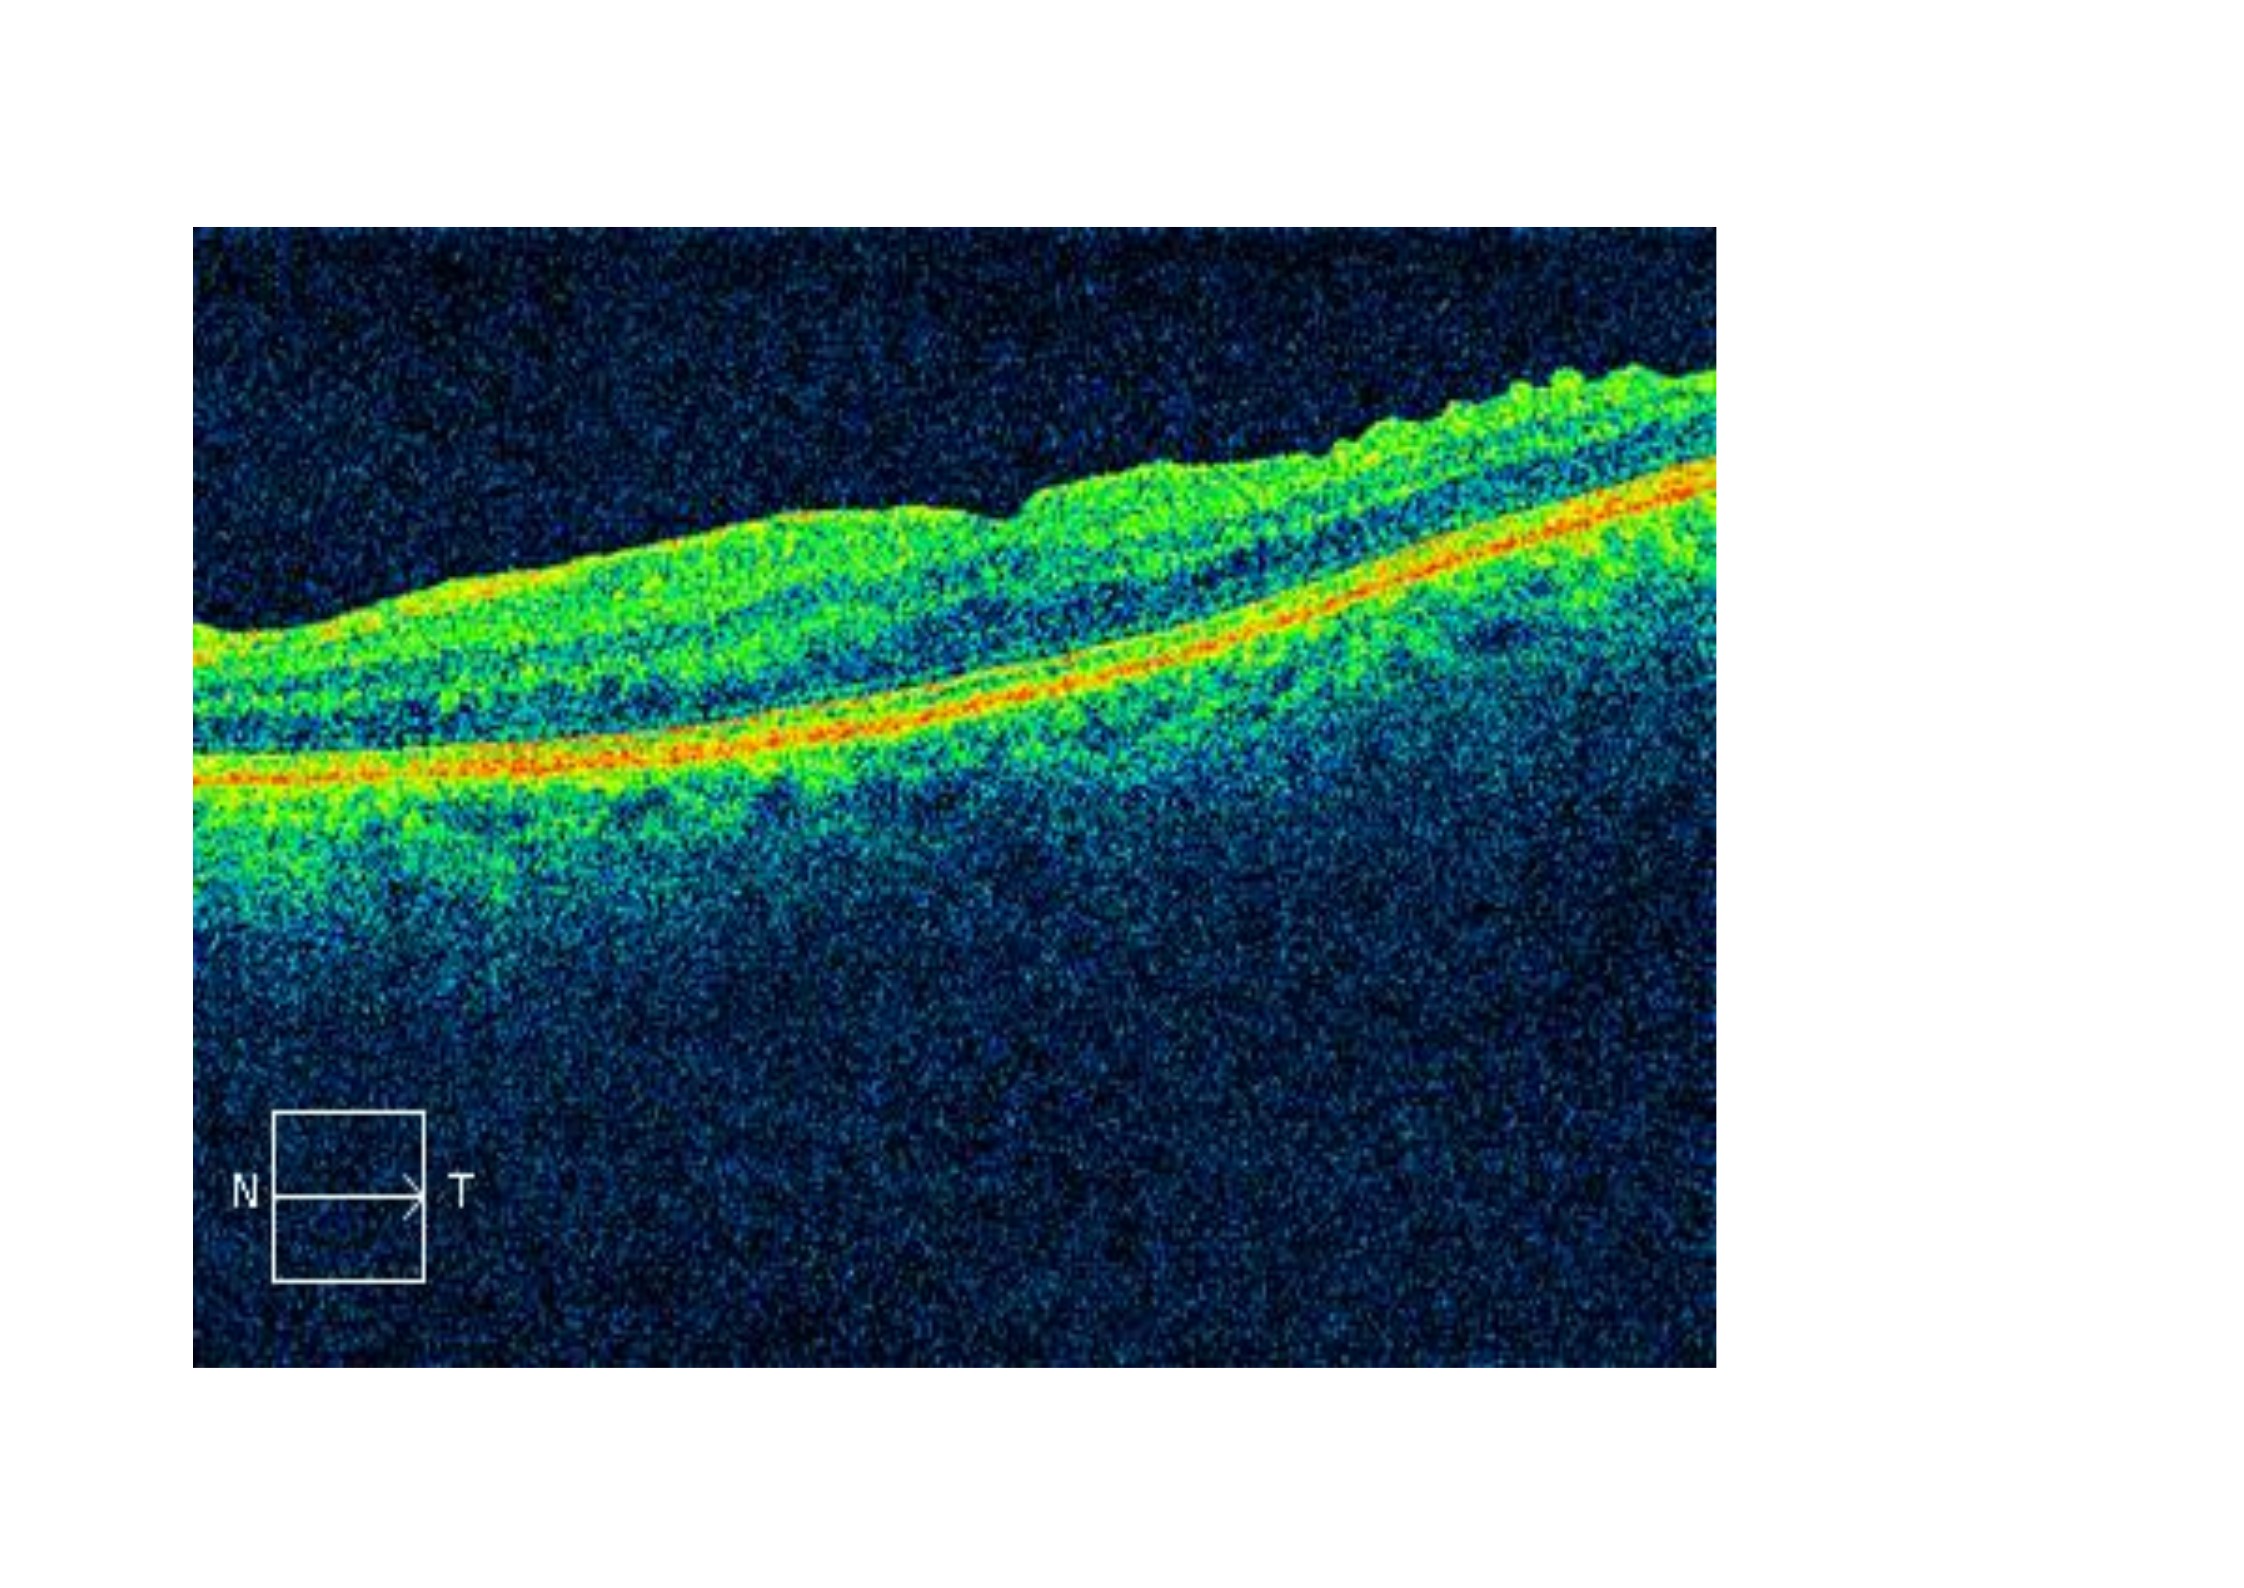

También las OCT pre y postoperatorios: